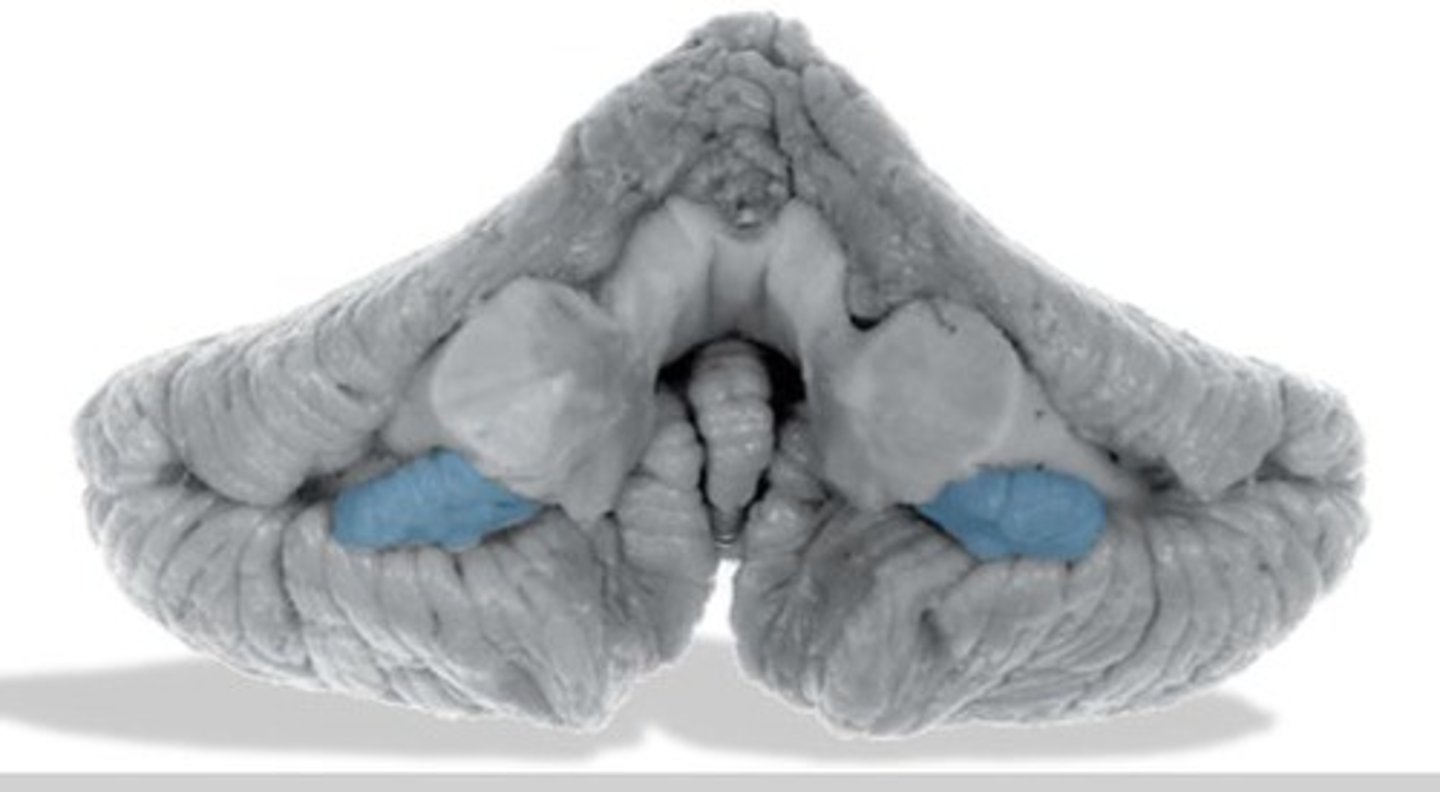

cerebellar peduncles

What information is transmitted via each peduncle?

Middle Cerebellar Peduncle:

Transmits cortico-ponto-cerebellar afferent fibers from the cerebral cortex to the cerebellum via the pons.

Superior Cerebellar Peduncle:

Transmits efferent fibers from the cerebellum to the red nucleus and thalamus, particularly the ventrolateral nucleus, which then influences the rubrospinal and corticospinal systems.

Inferior Cerebellar Peduncle:

Carries both afferent and efferent fibers. Afferents include spinocerebellar, medullocerebellar, and vestibular fibers, while efferents connect the cerebellum to the vestibular and reticular nuclei.